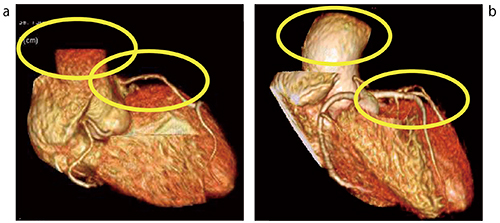

さらに,これらプリパルスの最適化とともにスライス特性の改善を目的としたRF波形の見直しを実施し,取得スラブ厚に対し有効視野の拡大が可能になった。これらを掛け合わせ,収縮期においても取得できるSPAIR法併用MRCAが使用可能になり,広範囲における矢状断面(サジタル)を用いることで大動脈情報を同時に取得するMRCA-Aoが取得可能になった(図2〜5)。

図2 新しいSPAIR法併用MRCA画像

a:CPR処理における左前下行枝(LAD)

b:三次元処理におけるMRCA-Ao

(画像ご提供:医療法人社団 CVIC 心臓画像クリニック飯田橋様)